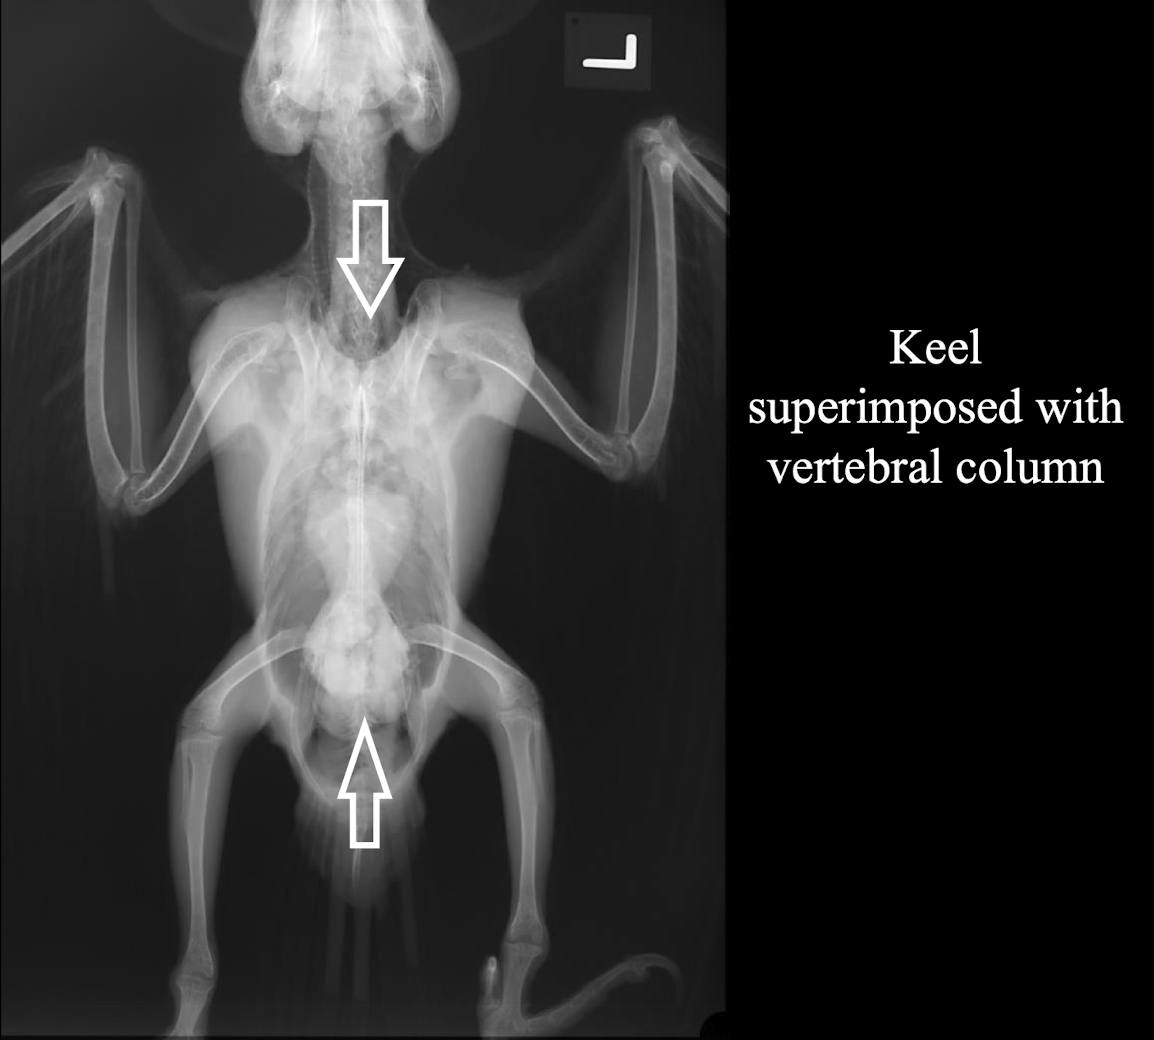

Correct radiograph positioning VD

Normal avian body xray

Lack of ultrasound windows due to the keel and air sacs → mostly just for echocardiography